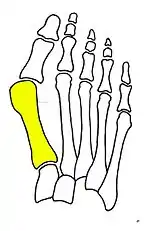

Primus varus deformity

Primus varus deformity is the leaning of the first metatarsal bone away from the second metatarsal and towards the opposite foot (Fig. 1). As it leans over, its head sticks out to form the bunion bump and it also widens the forefoot to cause shoes feeling too tight. Thus when bunion pain becomes unmanageable, surgical correction is to narrow the forefoot by repositioning of the first metatarsal head back to its normal position. This can be done by osteotomy (bone-breaking), soft tissue (non-osteotomy) or fusion techniques.